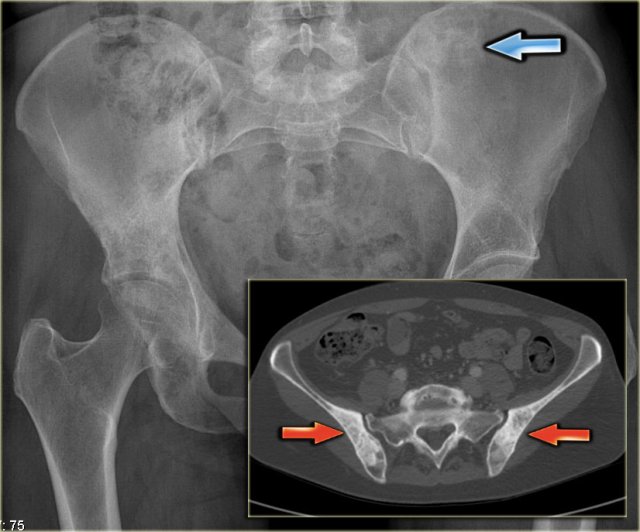

Here a radiograph of the pelvis with a barely visible osteoblastic metastasis in the left iliac bone (blue arrow).

Notice that CT depicts these lesions far better (red arrows).

Here CT-images of a patient with prostate cancer.

Notice the numerous ill-defined osteoblastic metastases.